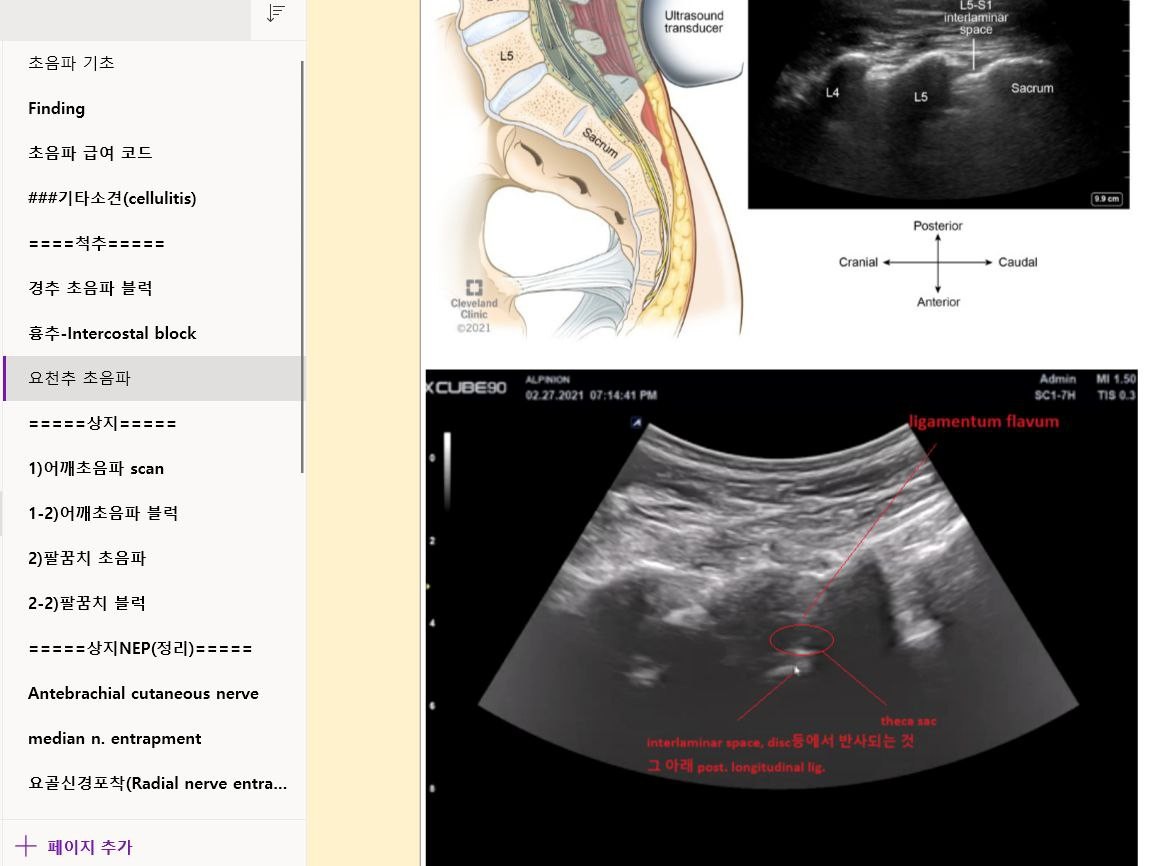

샘플 이미지